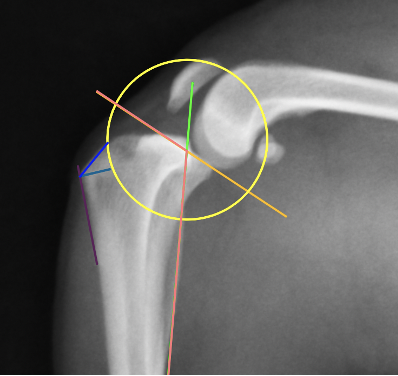

脛骨高平部角(TPA)と呼ばれる角度です。これが高いために前十字靭帯が切れやすくなります。

手術の際にはこのように様々な角度や距離を測定し、円の部分で骨切りを行います。